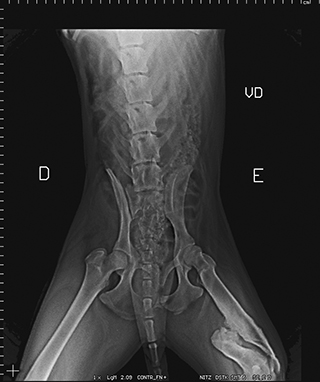

Radiologia Digital Direta / Digital Radiography

O treinamento aborda a geração das radiografias, a edição digital das imagens, e também a

escolha adequada de técnicas radiográficas como kilovoltagem, corrente elétrica e tempo de exposição.